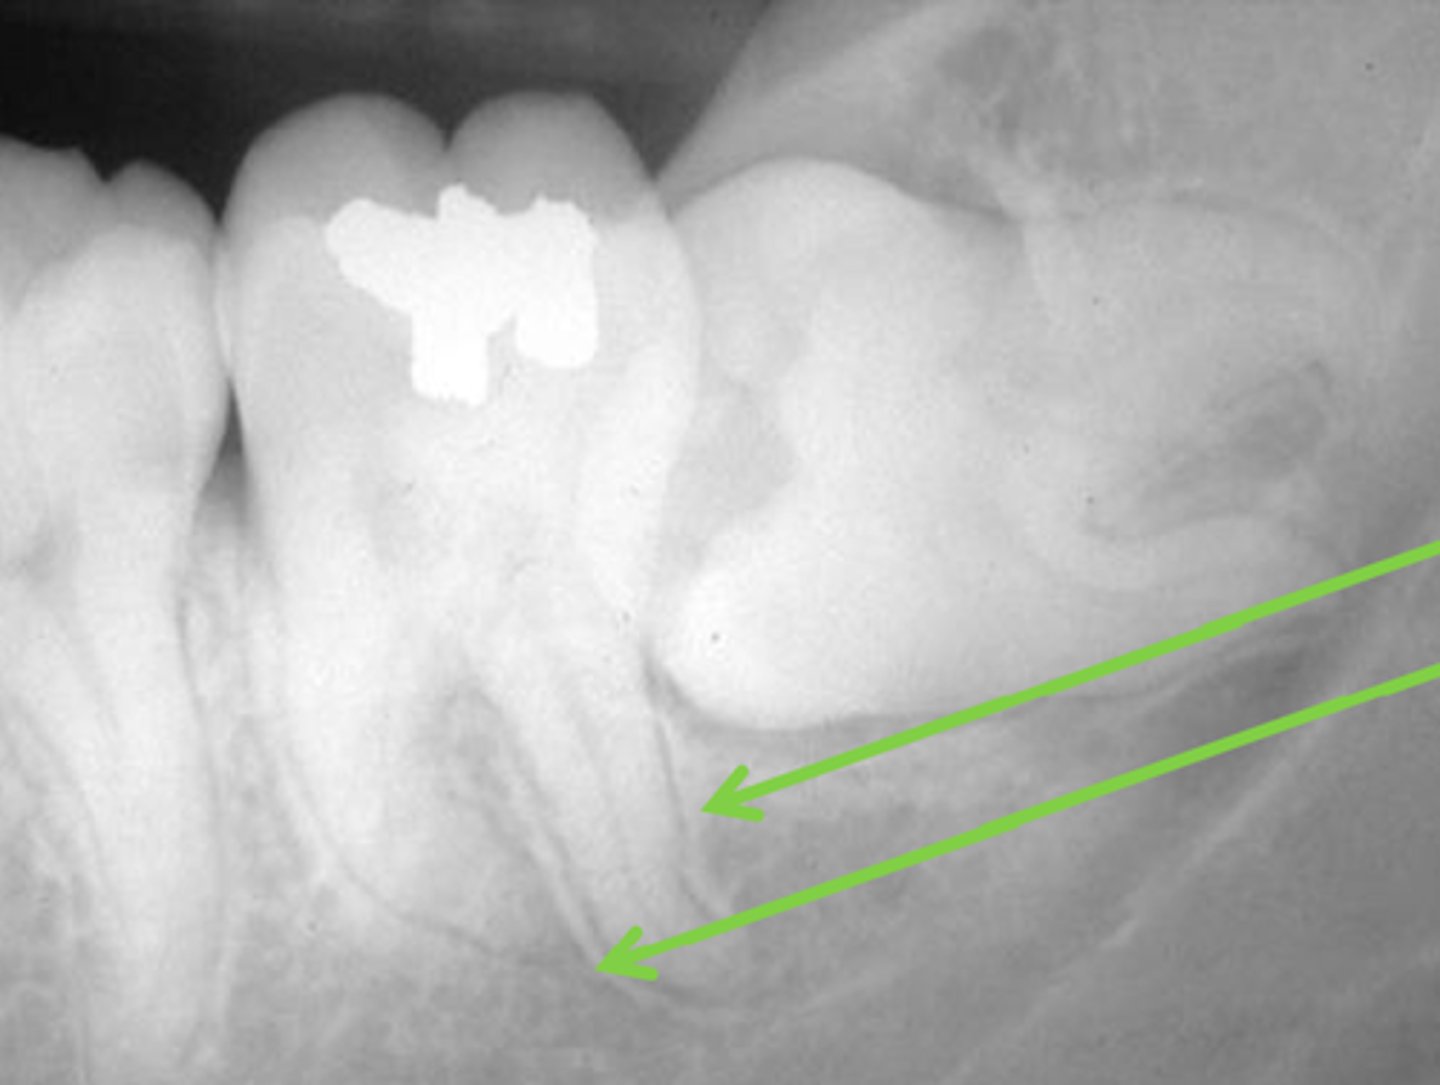

Which of these structures appears translucent?

Dental pulp

Does the Lamina Dura appear radiopaque/radiolucent?

Radiopaque

Does chronic abscess appear radiopaque or radiolucent?

Radiolucent